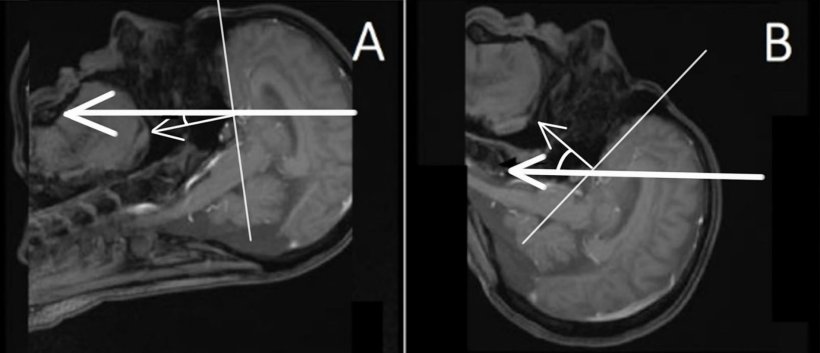

Bildquelle: Javor D, Leyer M, Ward BK et al., European Journal of Radiology 2026 (CC BY 4.0)

Ein Team unter der gemeinsamen Leitung von Prof. Dr. Domagoj Javor, Leiter des Instituts für Diagnostische und Interventionelle Radiologie am Universitätsklinikum Krems (einem Lehr- und Forschungsstandort der KL Krems) sowie Dr. Béla Büki von der dortigen HNO-Abteilung, untersuchte 20 gesunde Erwachsene ohne bekannte vestibuläre Erkrankung in einem 3-Tesla-Scanner. Die Fallzahl wurde bewusst klein gehalten; die Autorinnen und Autoren verstehen das Projekt als Machbarkeitsstudie, nicht als abschließende klinische Prüfung. Bei jeder Person wurden zwei hochauflösende Innenohr-Scans mit einer T2-gewichteten SPACE-Sequenz durchgeführt: einmal mit nach vorne geneigtem Kopf (Kinn zur Brust) und einmal mit nach hinten geneigtem Kopf (Überstreckung). Rekonstruiert wurde in der Ebene des horizontalen Bogengangs. Zwei erfahrene Mediziner arbeiteten unabhängig voneinander und „verblindet” und bestimmten, welcher Anteil des Vestibulums von den signalarmen „flow-void“-Arealen eingenommen wurde.

Physikalisch passen die Beobachtungen zu Modellen zur magnetischen vestibulären Stimulation. Bei zurückgeneigtem Kopf steht die Hauptrichtung ionischer Ströme im Innenohr eher senkrecht zum Magnetfeld des Scanners. Dadurch wird die Lorentz-Kraft größer, was stärkere Bewegungen der Endolymphe in Teilen des Innenohrs – insbesondere im Utriculus und im lateralen Bogengang – begünstigen kann. Solche Bewegungen können einerseits Strukturen beeinflussen, die zur Schwindelentstehung beitragen, und andererseits das MRT-Signal so verändern, dass ein ausgeprägterer „flow void“-Bereich entsteht.

Für den klinischen Alltag schlagen die Autorinnen und Autoren einen pragmatischen Umgang vor: Wenn in einer T2-Spin-Echo-Sequenz eine verdächtige vestibuläre Hypointensität auffällt, kann es helfen, zu prüfen, ob sie sich mit der Kopfposition oder zwischen verschiedenen Sequenztypen verändert. Gradient-Echo-Sequenzen, die weniger empfindlich auf langsame Flüssigkeitsbewegungen reagieren, können als Vergleich dienen. Zudem kann es die Links-Rechts-Vergleichbarkeit verbessern, die Kopfneigung in sagittalen Übersichtsaufnahmen zu dokumentieren und konsequent in der Ebene des horizontalen Bogengangs zu rekonstruieren. „Radiologinnen und Radiologen sollten wissen, dass diese charakteristische, rautenförmige Hypointensität im Vestibulum bei Kopfüberstreckung tendenziell zunimmt und bei Kinn-zur-Brust-Position abnimmt“, sagt Dr. Béla Büki. „Isoliert betrachtet kann sie wie eine fokale Läsion wirken – in vielen Fällen spiegelt sie jedoch lediglich Flüssigkeitsbewegung im starken Magnetfeld wider.“